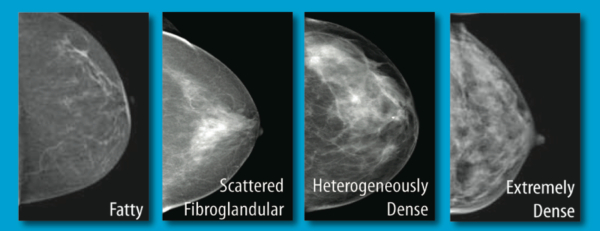

• Breast Density